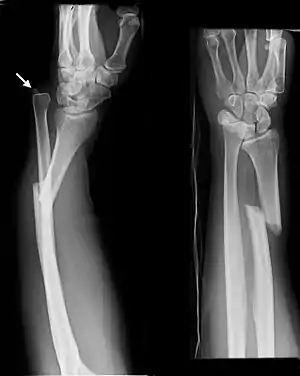

- Monteggia fracture - a fracture of the near to elbow end of the ulna with the dislocation of the head of the radius at the elbow joint.[2]

Monteggia Fracture (fracture of proximal ulna)